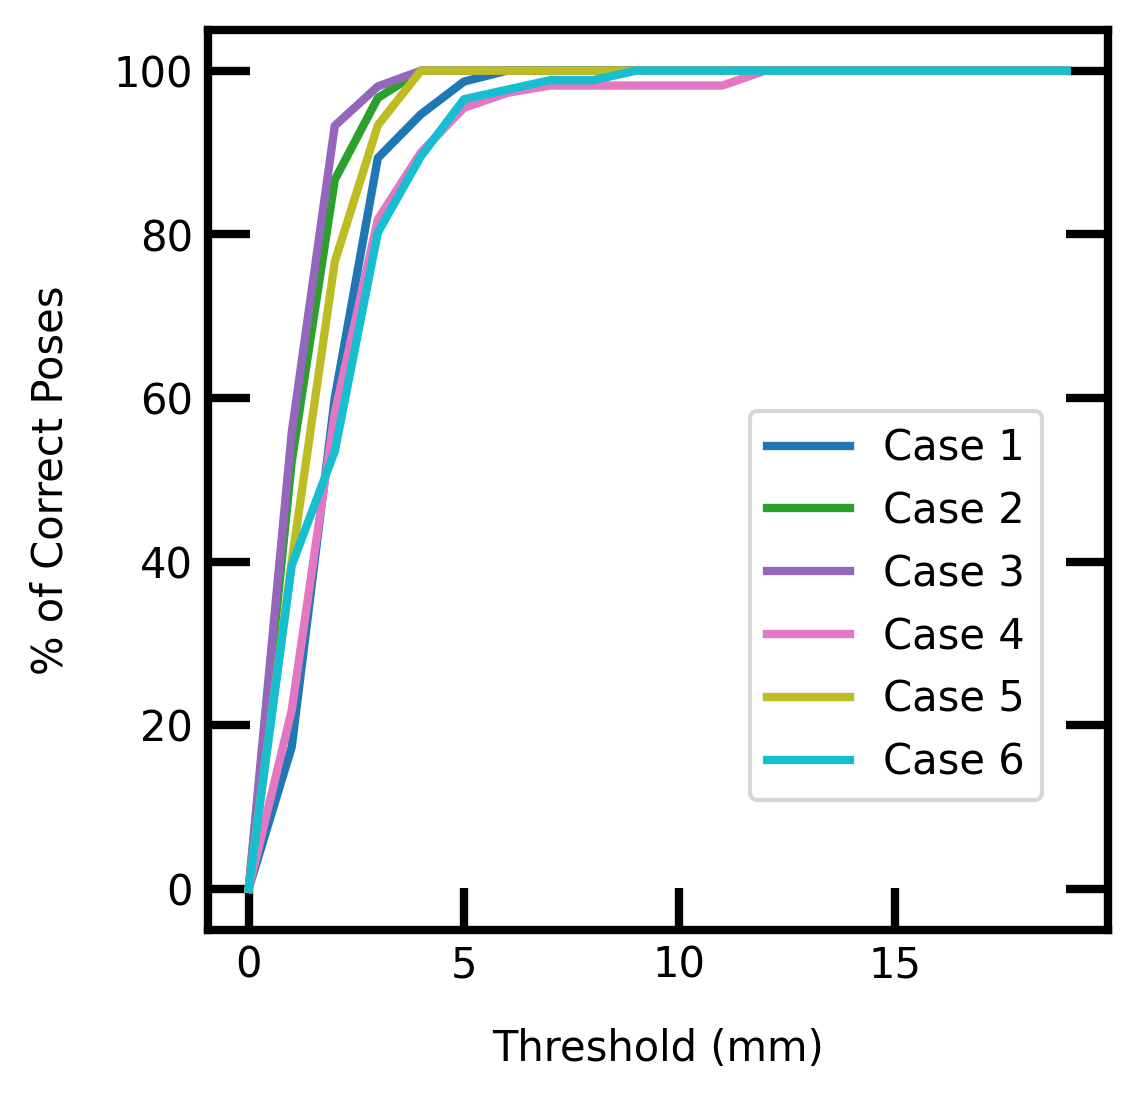

Accuracy-threshold Curves

We calculated the number of ’correct’ poses estimated by our model. We varied the distance threshold on the validation sets (excluding 2 textures) in order to reveal how the model performs w.r.t. that threshold. We plotted accuracy-threshold curves showing the percentage of pose accuracy variation with a threshold in a range of mm to mm. We can see in Fig. 3 that a % pose accuracy was reached within the 3mm-3deg threshold for all cases. This accuracy increases to % with a 5mm-5deg threshold.